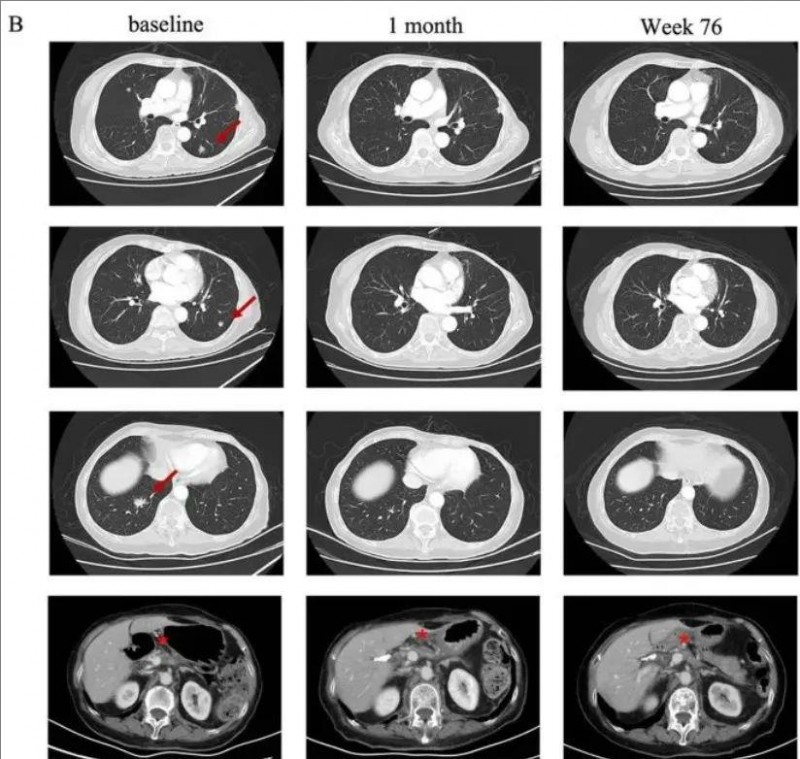

2023年9月21日,科济药业宣布该公司自主研发的靶向Claudin18.2的CAR-T细胞CT041治疗转移性胰腺癌的两个病例报告已发布在9月9日的《血液学与肿瘤学杂志》期刊上。

值得一提的是,这两则典型病例很具有代表性,全部都是化疗失败、全身转移、经历过一二线治疗失败的难治性胰腺癌患者。在参加实体瘤CAR-T疗法CT041临床试验后,均得到不同程度的肿瘤病灶大幅度缩小,甚至完全消失!再次印证了这款里程碑式CAR-T疗法的惊艳疗效!

▲截自《Journal of Hematology & Oncology》

典型病例1

一名58岁的女性胰腺癌患者,伴有肺及淋巴结转移。该患者先后经历一线白蛋白紫杉醇联合吉西他滨和二线伊立替康联合5-氟脲嘧啶治疗后失败。经检测其Claudin18.2表达为2+/70%后入组CT041临床试验。

在进行氟达拉滨、环磷酰胺、白蛋白紫杉醇方案清淋预处理后,患者于2021年9月接受CT041细胞输注。输注后患者出现2级细胞因子释放综合征(CRS),在接受托珠单抗后恢复。根据RECIST v1.1标准,患者肿瘤评估达到部分缓解(PR),肺部转移灶明显缩小。

典型病例2

一名75岁的高龄女性胰腺癌患者,于2019年5月接受了手术切除,诊断为pT2N0期胰腺癌。术后随访5个月时发现肺转移。自2019年12月开始一线S-1单药化疗,在行手术野姑息性放疗期间肺部转移。经检测其Claudin18.2表达为3+/60%后入组CT041临床试验。

在进行氟达拉滨、环磷酰胺、白蛋白紫杉醇方案清淋预处理后,患者于2021年7月输注CT041细胞输注。输注后患者出现2级CRS,经托珠单抗治疗后恢复。患者在CT041输注后第4周进行首次肿评即达到部分缓解(PR),后肺部靶病灶进一步消失达到完全缓解。截至2023年7月末次随访时患者仍处于持续缓解状态。

权威肿瘤专家表示:此次CT041的初步数据显示,CAR-T疗法对胰腺癌的治疗具有相当大的潜力,即使是对既往多种治疗方案失败的患者也是如此。希望CT041在将来有可能改变胰腺癌和其他实体瘤的治疗格局,让我们拭目以待!